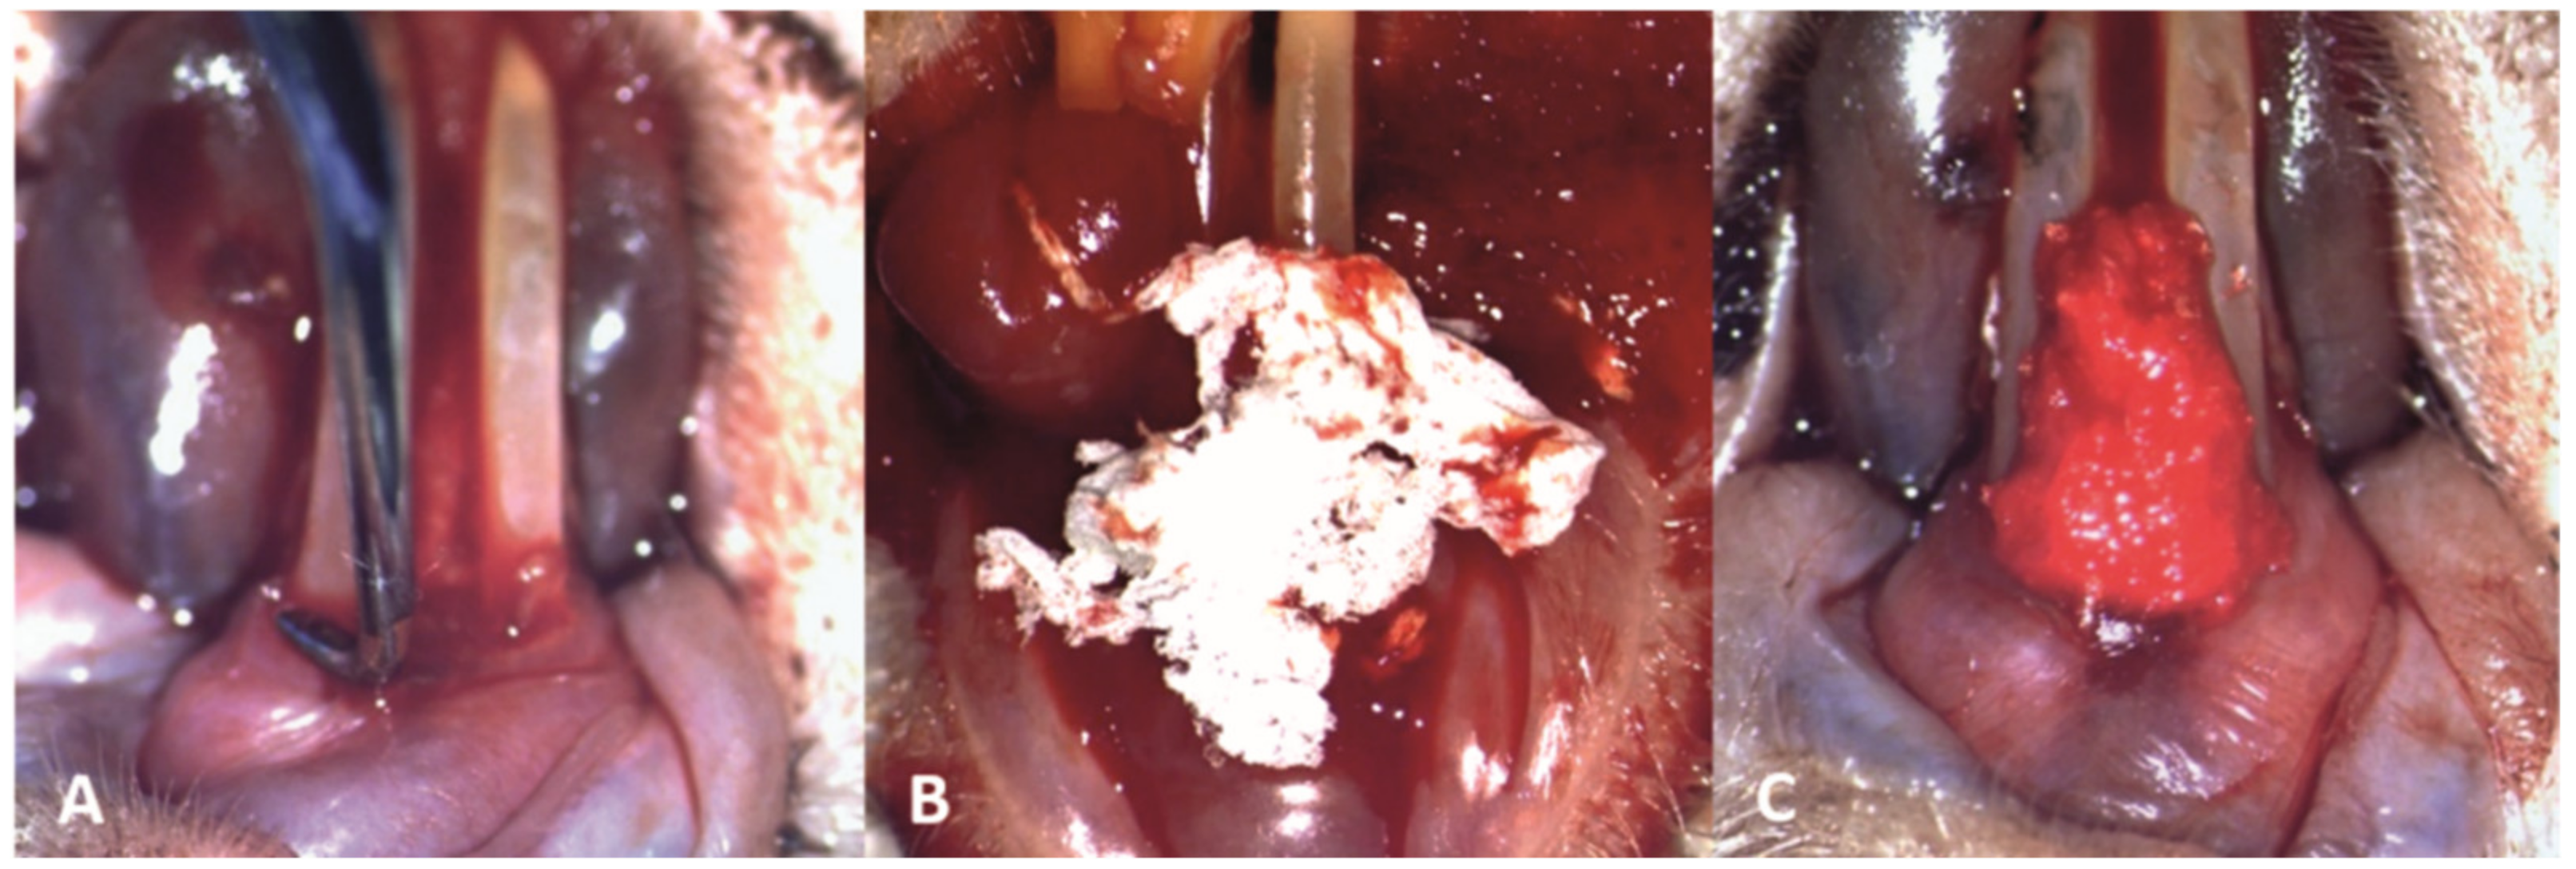

The mechanical debridement was performed gently to the subjects in groups T1 and T2, using the modified Gracey curette, in order not to cause damage to the inflamed periodontal tissues (Figure 4A). Subsequently, in subjects from the T1 group, the novel biomaterial was applied in the periodontal pockets on the buccal, distal and mesial surfaces of the teeth, and interdentally between the two lower incisors (Figure 4B,C).

Figure 4.

Clinical aspect of the periodontal treatment (10× magnification): (A) mechanical debridement of the lower incisors; (B) application of the novel biomaterial obtained through electrospinning; (C) final aspect of the material applied at a sulcular level and interdentally between the two lower incisors, saturated with blood and promoting local hemostasis.